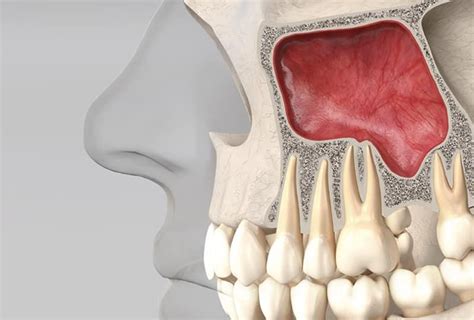

En la arcada superior, entre otras técnicas, también podemos pensar en la regeneración ósea y los injertos sobre proceso residual para conseguir cresta alveolar, o bien obtener este hueso que nos falta por medio de la elevación sinusal y relleno con material de injerto.

Con la técnica de elevación sinusal y relleno de biomaterial, podemos conseguir el hueso que podamos necesitar para anclar las fijaciones de la prótesis que vayamos a realizar. Sólo es necesario un mínimo de altura ósea entre el suelo sinusal y el reborde alveolar para que se consiga un anclaje estable de las fijaciones, de lo contrario, si no tenemos estabilidad primaria resulta más difícil la osteointegración de las fijaciones. Algunos autores han intentado establecer unos requerimientos mínimos de altura ósea en el proceso residual alveolar para conseguirse esta estabilidad y por tanto un buen resultado de osteointegración.

Si además de tener una altura mínima de hueso por debajo del seno maxilar, la anchura de éste es escasa, se nos complican las cosas para el anclaje de los implantes, debiendo pensar en las posibilidades que tenemos de ensanchamiento de la cresta, entre las que se encuentran la regeneración ósea con membranas, la utilización de biomateriales en diferentes técnicas y formas de presentación, además de la posibilidad de emplear plasma rico en plaquetas como método de conseguir hueso o como complemento de las demás técnicas.

¿En qué pacientes se realiza la elevación del seno maxilar?